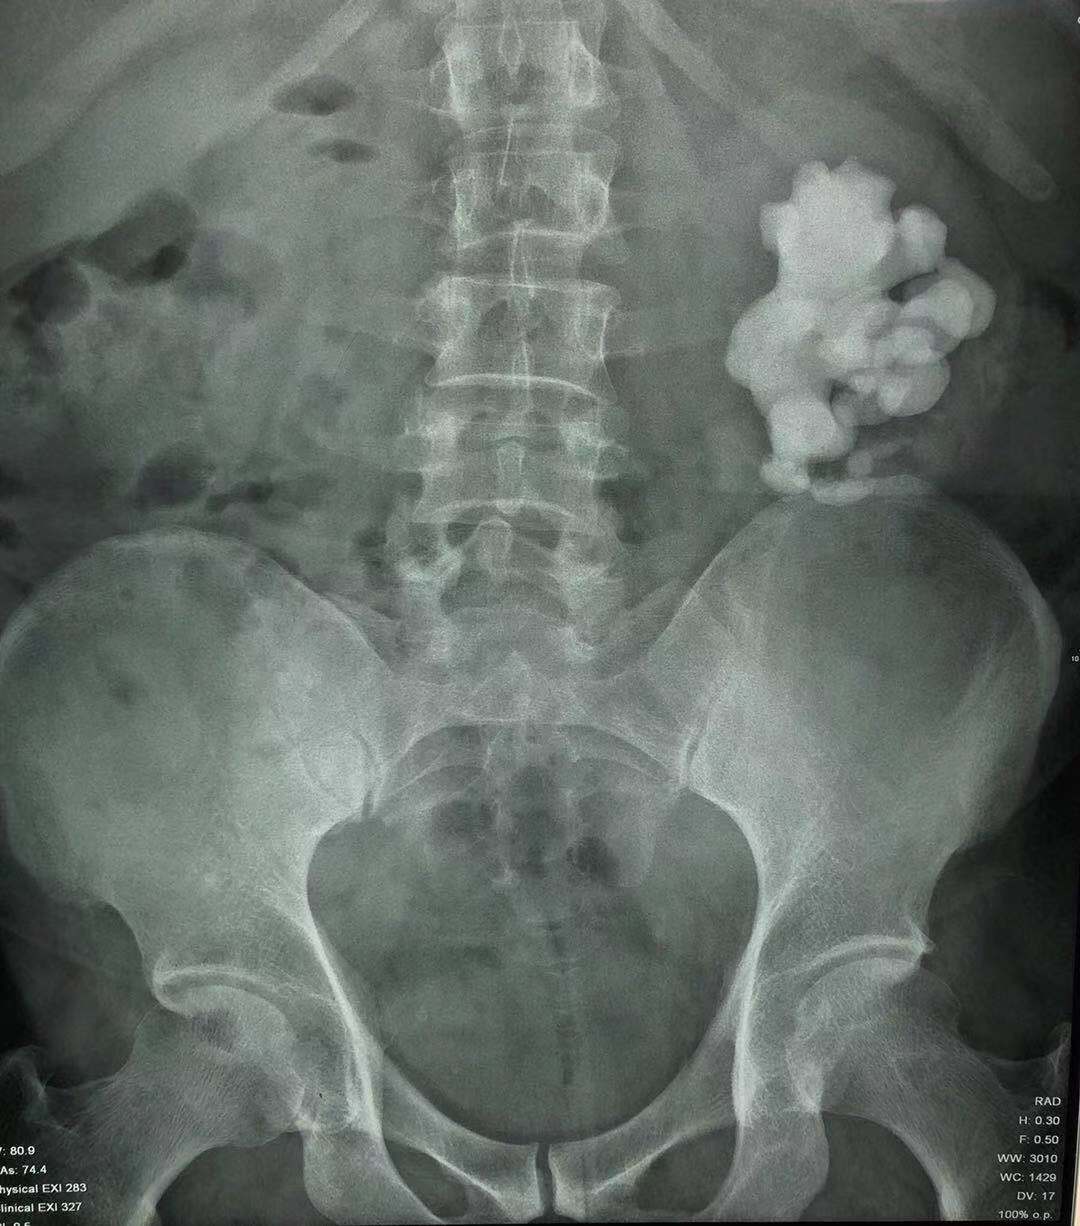

左侧肾脏的鹿角形结石

林先生的双肾鹿角形结石